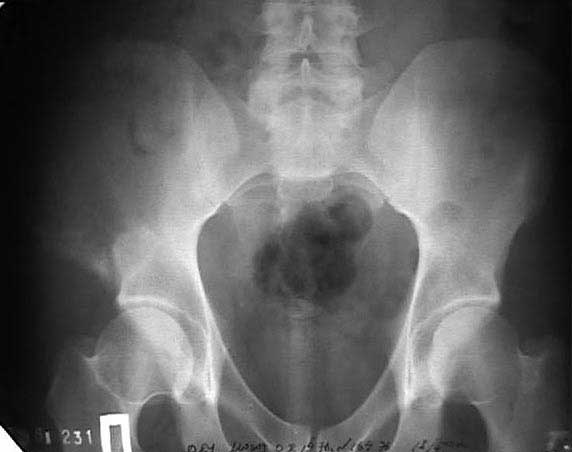

В 2002 году буквально "промелькнул" и исчез пациент с подобным остеолизом. Обследован (биопсия ) в отделении костной онкологии, а затем у дерматологов. Причиной остеолиза признан актиномикоз. К сожалению в то время не удалось выполнить КТ, а рентгенограммы не качественные - в приложении.

Имя     : 16.04.02.jpg

Тип     : image/jpg

Размер  : 30581 байтов

Url     : http://weborto.net:8080/pipermail/ortho/attachments/20110406/5444d703/attachment-0005.jpg